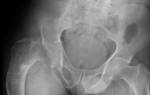

Как выполняется диагностика кист яичника?

Предположение о возникновении кисты яичника может сделать врач даже при обычном ручном осмотре. Однако для постановки точного диагноза кисты всегда назначается ультразвуковое исследование. УЗИ яичников позволяет точно определить локализацию и размеры кисты, сделать предположения о ее типе и о необходимости хирургического вмешательства или применении консервативной терапии. Обычно на УЗИ киста яичника представлена в виде анэхогенного образования – темного пятна.

Иногда кисту яичника может обнаружить врач во время бимануального гинекологического исследования. Если наличие кисты подозревается на основании симптомов или физикальной диагностики, то могут быть рекомендованы визуальные диагностические процедуры. Большинство кист диагностируются ультразвуком — это лучший метод для выявления таких образований.

Он предполагает использование звуковых волн для создания изображений структур, находящихся внутри тела. Ультразвуковое исследование безболезненное и безвредное. Трансвагинальный ультразвук — диагностический инструмент, используемый для лучшей визуализации яичников при помощи тонкого ультразвукового зонда, который вводится во влагалище.

— Ультразвуковая диагностика (УЗИ). Является наиболее информативным методом выявления кисты яичника. Проводится при помощи трансвагинального датчика.